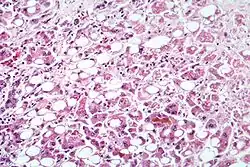

Mikroskopický snímek jater, která byla poškozena hepatitidou způsobenou nadměrným pitím alkoholu.

Hepatitida (latinsky hepatitis) je zánět jater. Může být infekční nebo neinfekční povahy, akutní či chronický.